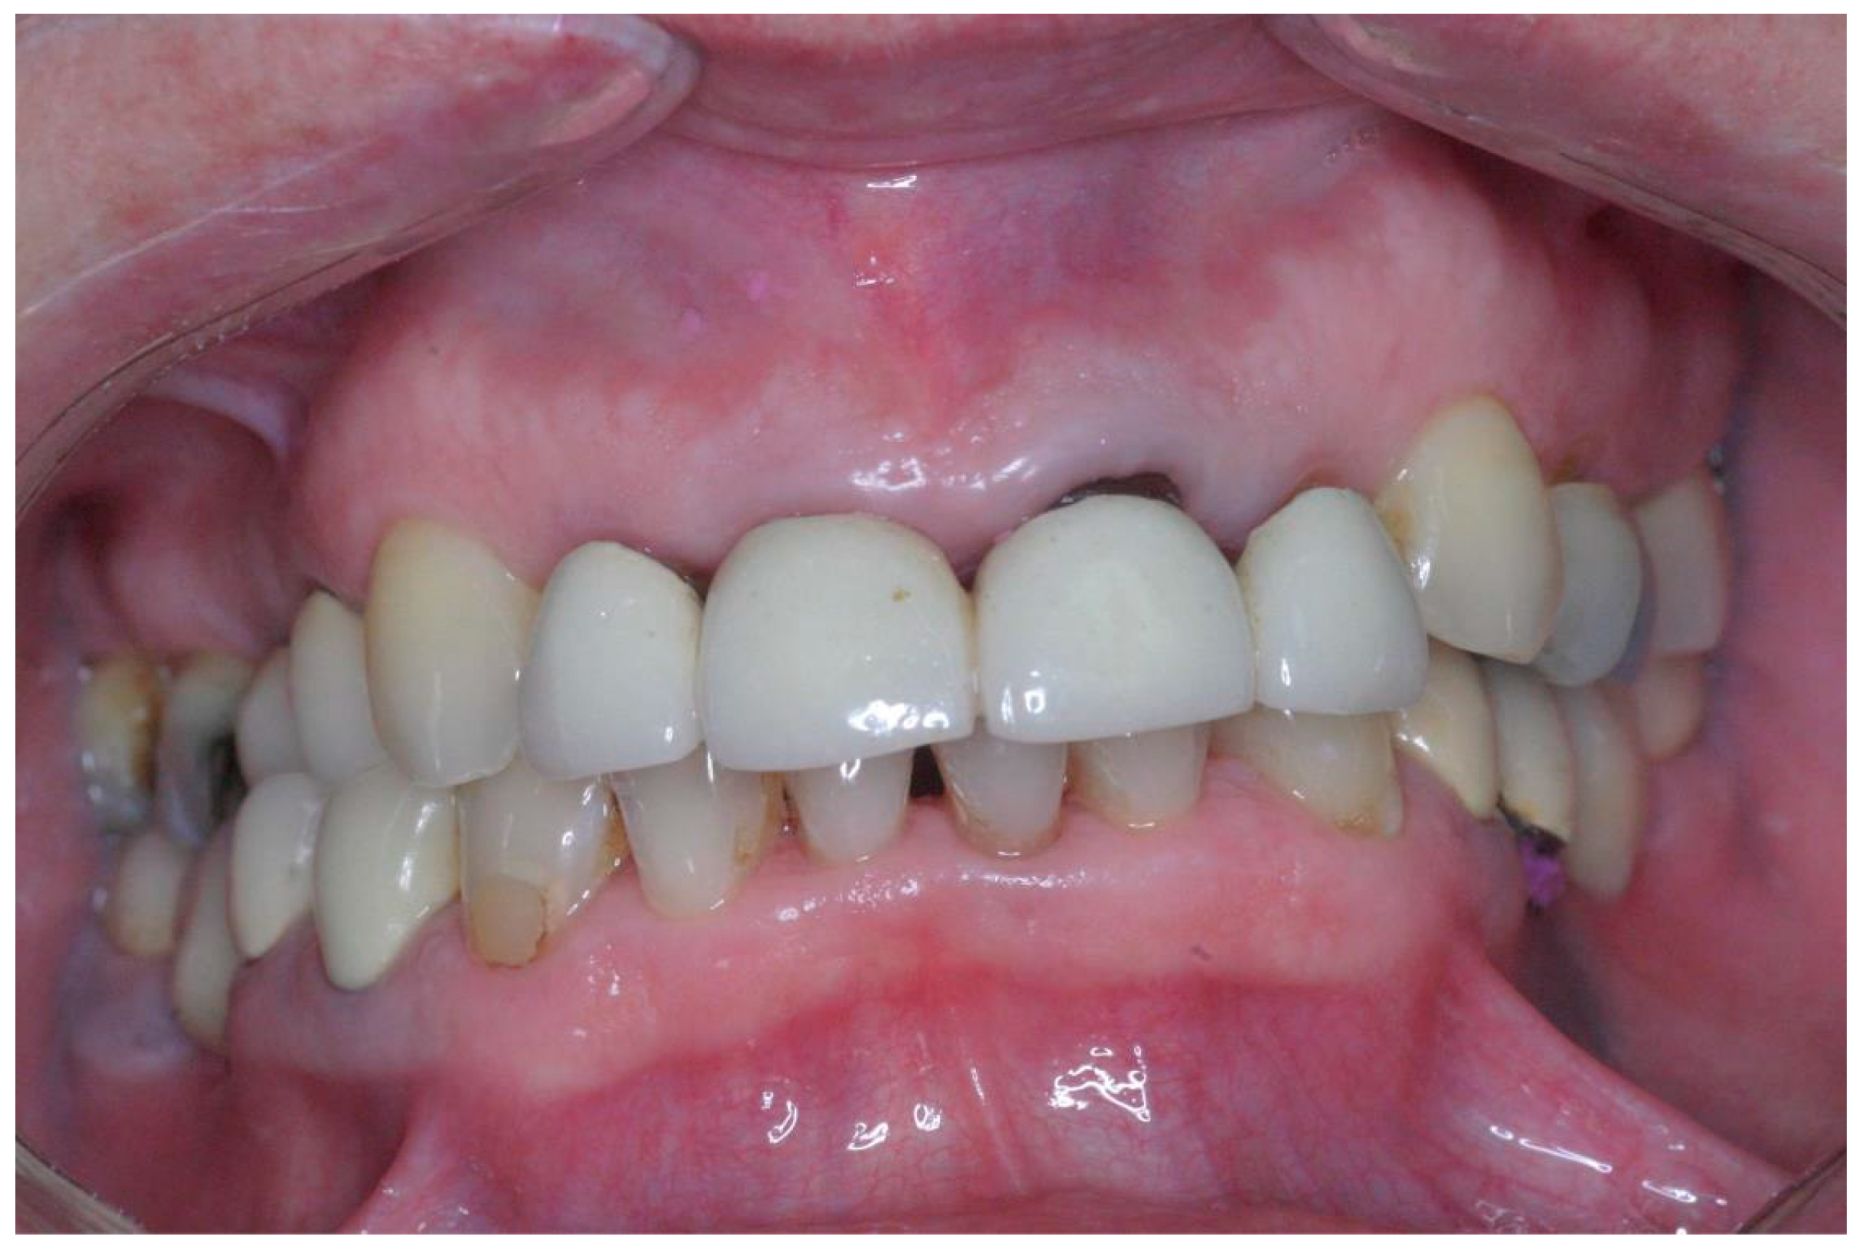

2.3.2. Reconstructive Treatment Protocol

A master model with a silicon image of the marginal gingiva as well as individual abutments and reinforced temporary bridges were prepared within 24–72 h. The temporary bridge was contoured to mirror the removed tooth, with open embrasure spaces aiming to promote complete papilla formation. Transfer abutments were replaced by individual abutments, followed by the adaptation of a prefabricated non-functional acrylic temporary bridge with minimal occlusal contacts in intercuspal position [IC] but not contacts in protrusive and lateral movements (Figure 3). Implants were considered successful if they fulfilled the criteria of Alberktsson and colleagues [43]. The final zirconia or ceramic bridge restorations were performed six months after implant placement. The final bridge was designed to permit interproximal cleaning (i.e., no attempt was made to fill interproximal spaces with ceramics).

Figure 3.

Pre-fabricated non-functional metallic re-enforced acrylic temporary bridge placed 48 h after implant placement.